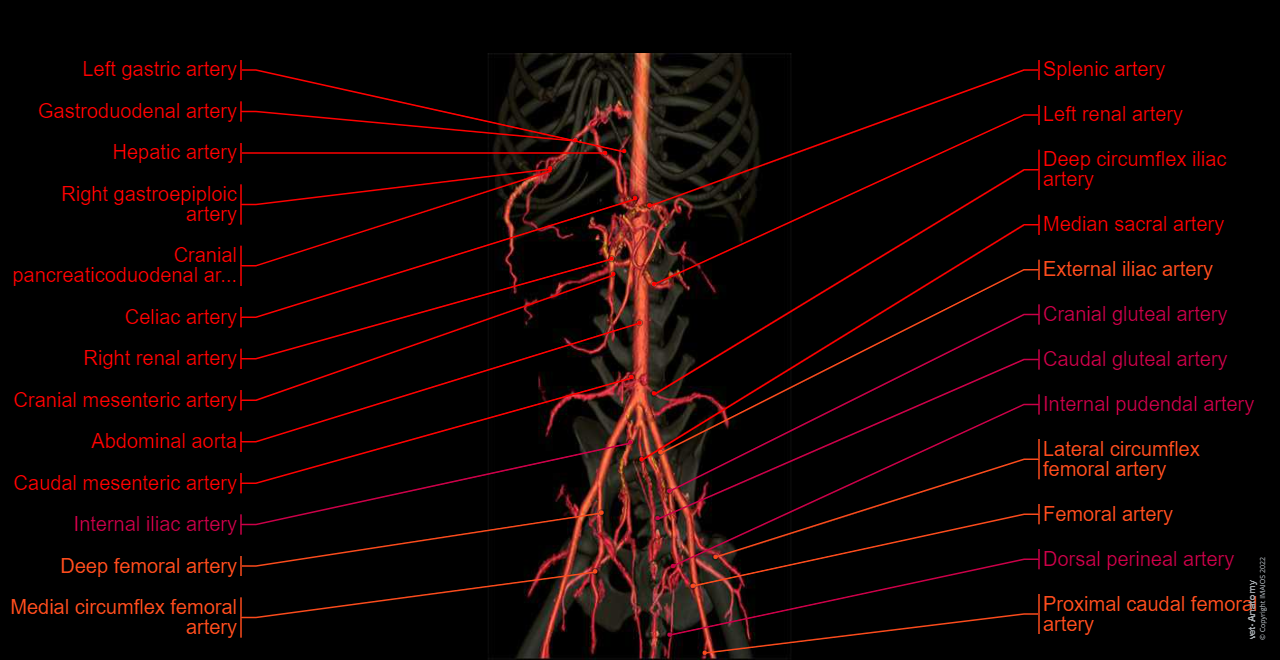

Dog - Abdominal aorta - Anatomy - 3D: Celiac artery, Splenic artery, Hepatic artery, Cranial mesenteric artery, Caudal gluteal artery, Internal pudendal artery